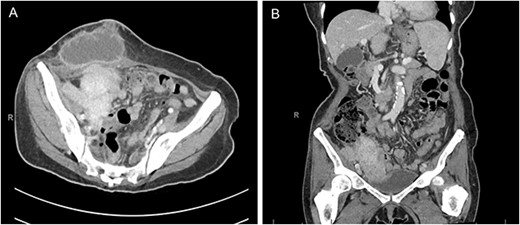

Physical exam was notable for diffuse abdominal tenderness to palpation and an indurated right lower quadrant mass with surrounding warmth and erythema. Laboratory studies on admission included a white blood cell count of 16.2 × 109/L with 92% neutrophils. Blood and urine cultures were negative. Computed tomography of the abdomen and pelvis demonstrated a 7.8 × 4.3 cm right lower quadrant mass abutting the right pelvic sidewall and a superficial fluid collection in the anterior abdominal wall with a cutaneous fistula (Fig. 1). Due to initial concern for malignancy, a biopsy was obtained at an outside hospital that demonstrated confluent sheets of histiocytes with eosinophilic cytoplasm (von Hanseman cells) and intracytoplasmic periodic acid-Schiff positive basophilic inclusions (Michaelis–Gutmann bodies), consistent with malakoplakia.

Computed tomography of the abdomen and pelvis in the axial (A) and coronal (B) planes demonstrating a 7.8 × 4.3 cm mass along the right pelvic sidewall and necrotic mass in the anterior abdominal wall with a cutaneous fistula.